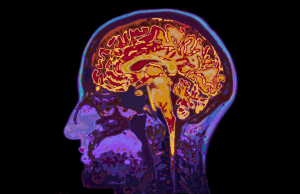

Brain cells depend on a steady supply of nutrients and antioxidants to keep them healthy and functioning efficiently. Poor nutritional status can interfere with production... Continue reading